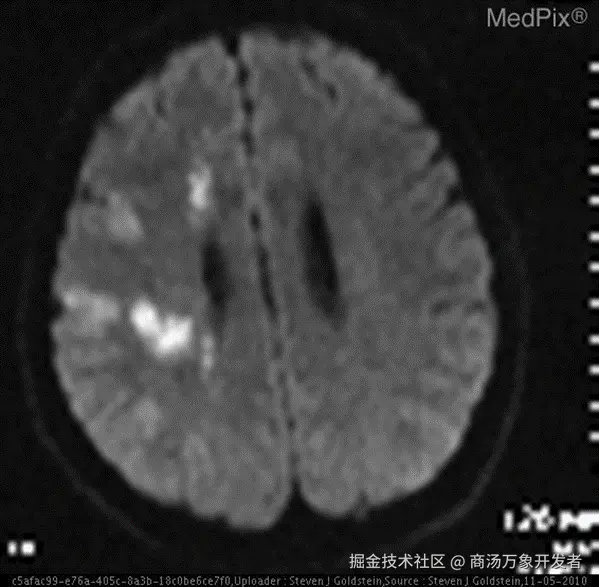

7826f6ad0b05e0681f35646cda1425a1.png

当医生拿着CT片问AI:"这片脑区有梗塞吗?"

• 普通AI:"抱歉,我无法提供诊断建议" ❌(急死个人!)

• ​LlamaFactory微调后的AI​​:"右侧基底节区可见低密度灶,考虑急性梗塞" ✅(专业!)

​想知道怎么让AI从"小白"变身"影像科大神"吗?​​ 跟我一起探索吧!